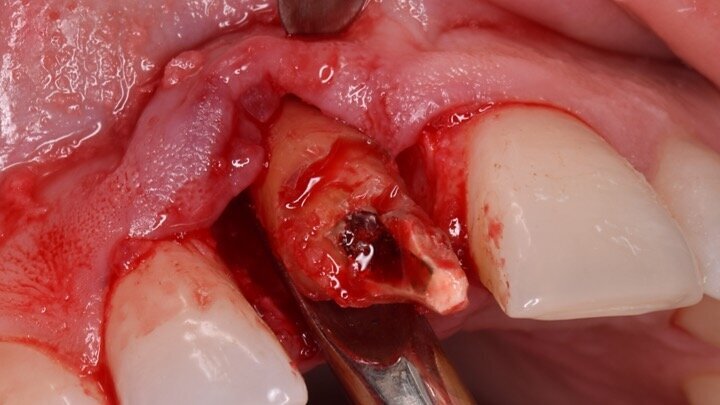

Figura 1. Atrofia de más del 50% de la pared vestibular en el diente 11 con infecciones de repetición de varios años de evolución.

Figura 6. A pesar del defecto óseo, siempre buscamos la posibilidad de crear un nuevo alveolo quirúrgico que emerja por la zona del cíngulo de los dientes adyacentes, es decir, el margen de emergencia adecuado. En estos defectos, intentamos siempre el anclaje en profundidad con implantes largos de unos 16 mm debido al gran defecto existente. Es la única forma de que la estabilidad primaria del implante permita realizar una Prótesis Inmediata.

Figura 7. Implante de conexión interna insertado 2 mm por debajo de la cresta ósea, independientemente del defecto existente y a 55 Nw. Al no existir margen vestibular, tomamos como referencia los dos picos óseos de las papilas y entre ellos trazamos una línea imaginaria que los una enterrando el hombro unos 2 ó 3 mm por debajo de ella.